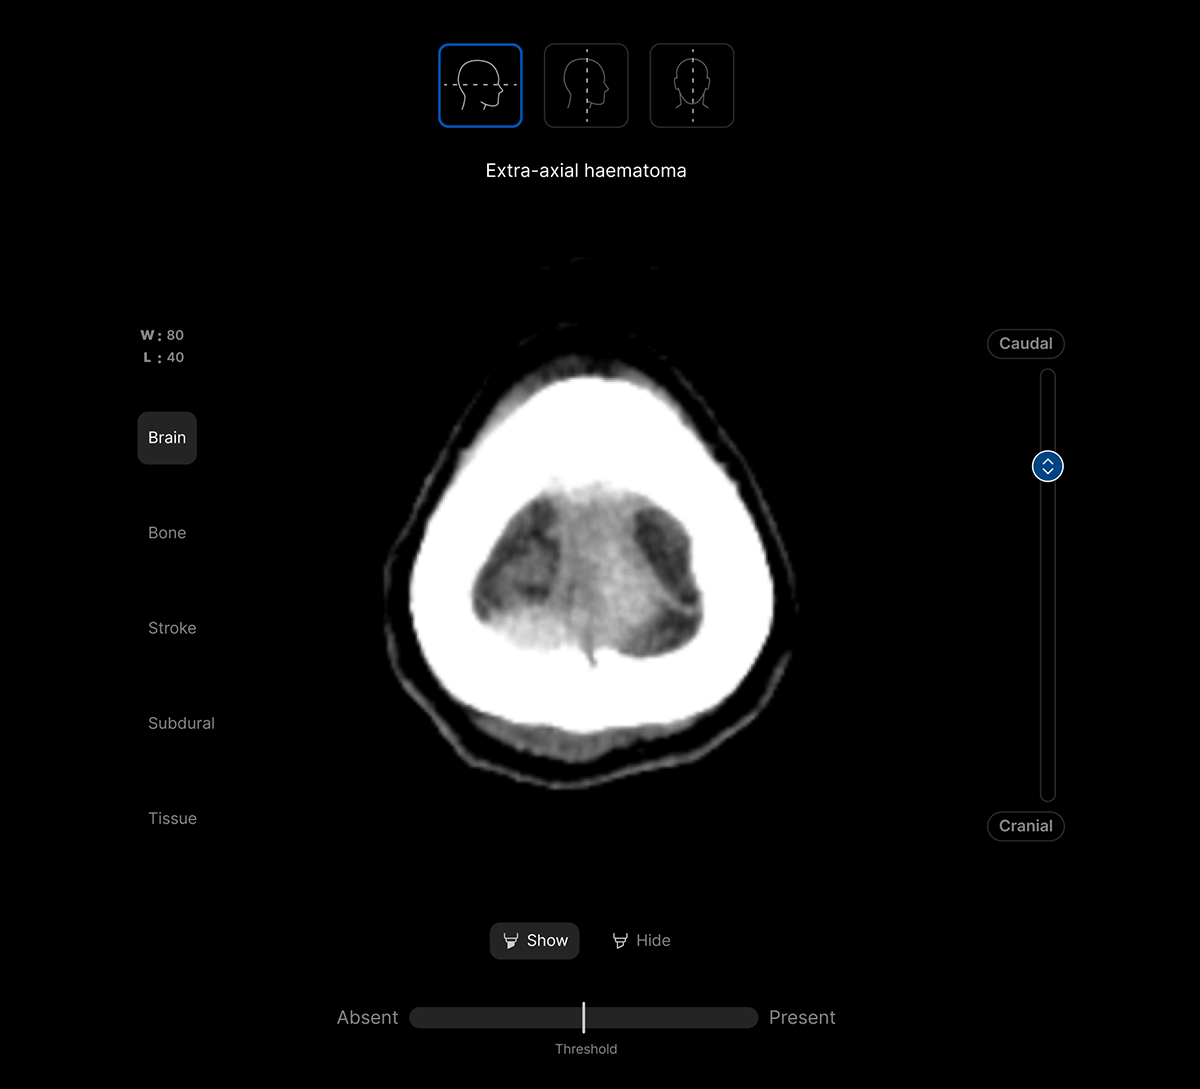

Customisable features.

Customisable thresholds, for individual findings (to optimise for sensitivity / specificity) to tailor the workflow to your clinical setting or population.

Intelligent worklist prioritisation.

Optimise care pathways with AI-powered Worklist Prioritisation.

- Cases are automatically analysed as soon as they’re acquired and AI results are available within 90 seconds.

- Flag patients with urgent findings.

- Configurable study priority groups for customised workflows.